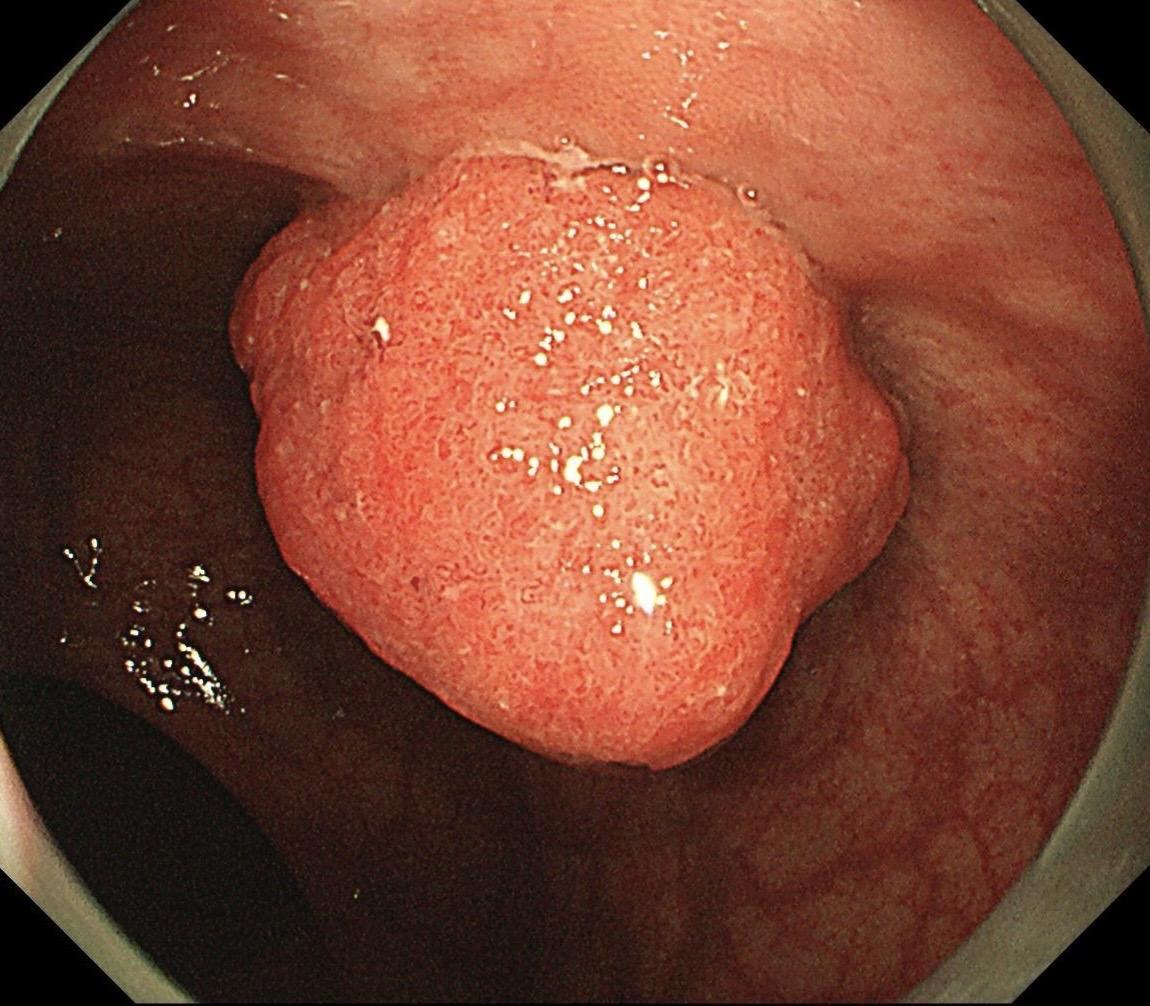

哇哦,树莓哎。小凹上皮肿瘤伴高级别上皮内瘤变,日常工作中并不常见,可惜...